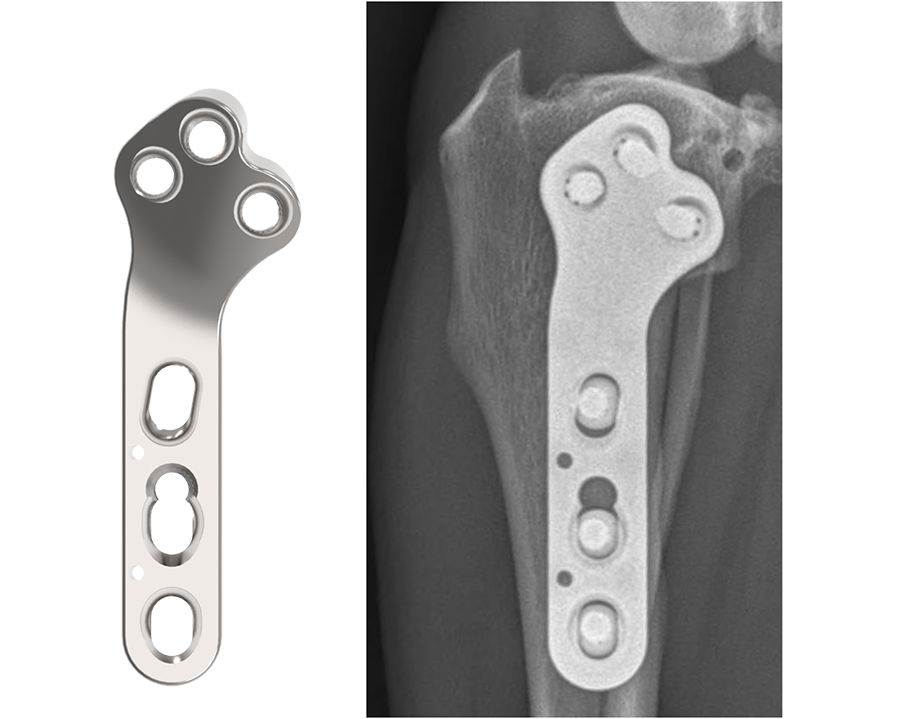

3.5mm TPLO Plate with Advanced Radial Compression (ARC)

The DePuy Synthes TPLO System is meticulously designed for stabilizing osteotomies of the canine proximal tibia, ensuring stable fixation and reliable healing. Developed in collaboration with and approved by the AO Technical Commission, the ARC TPLO plate comprises two 3.5mm plates, for both left and right applications.

This innovative system is engineered to deliver precise compression across the osteotomy, leveraging specialized compression holes along the shaft. This targeted compression not only fosters direct bone healing but also bolsters resistance against potential rock-back failures. Moreover, it streamlines the contour of the proximal plate and optimizes screw placements, reducing the necessity for plate contouring while ensuring dependable locking screw positioning. The design features a consistent locking interface between the plate and the locking screws, reinforcing stability and integrity.

The ARC TPLO plate stands out for its continuous, precisely directed compression across the osteotomy site. Notably, the proximal section of the ARC TPLO plate is slightly angled in a more caudal direction to accommodate diverse patient anatomies. Furthermore, the trajectories of proximal locking screws are designed to steer clear of the articular surface while engaging the central mass of the proximal tibia, ensuring optimal fixation and stability.